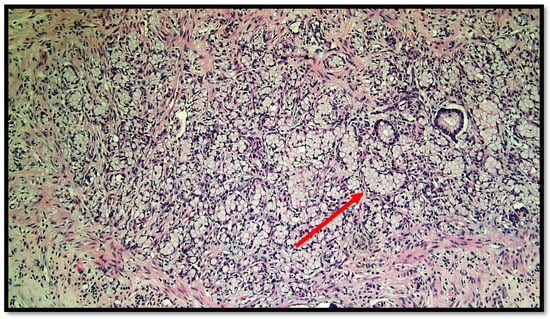

Figure 4.

Details of muscular invasion by GCC of the appendix (hematoxylin–eosin, original magnification 20×).